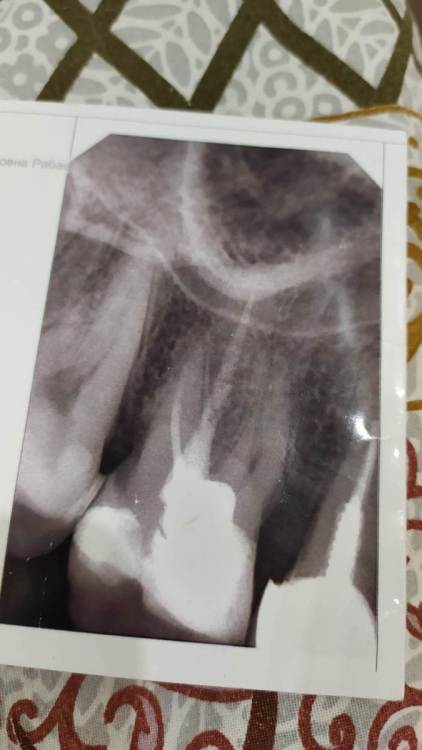

Рабин Опубликовано 2 апреля, 2021 Поделиться Опубликовано 2 апреля, 2021 Уважаемые врачи по снимкам вы видите воспаление или кисту на зубе? Спасибо! Ссылка на комментарий

сирена Опубликовано 3 апреля, 2021 Поделиться Опубликовано 3 апреля, 2021 5 часов назад, Рабин сказал: Снимки не показательны? Иногда на прицельном снимке ничего криминального не видно,а на КТ обнаруживается очаг. Можно маленькую КТ сделать,только в области этого зуба(5Х5 см) 2 Ссылка на комментарий

Рабин Опубликовано 18 мая, 2021 Автор Поделиться Опубликовано 18 мая, 2021 Добрый день! Сделала КТ этого зуба, как вы просили... https://cloud.mail.ru/stock/kkbze24nzBzfEqnUbdPwtsei Видите ли вы воспаление на нём и можно ли его спасти? Интересует также соседний 15 зуб. Спасибо! Ссылка на комментарий